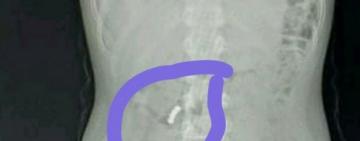

9 успешных трансплантаций органов за 2 дня провели украинские хирурги

За последние два дня украинские хирурги успешно провели девять операций по тр...